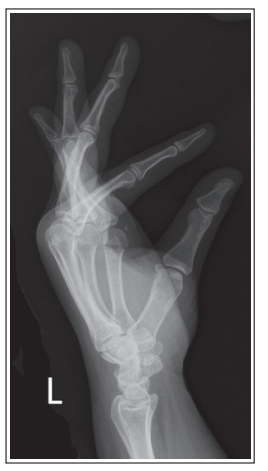

What is wrong with this oblique wrist xray

Under-rotated

Less than 45 degree obliquity